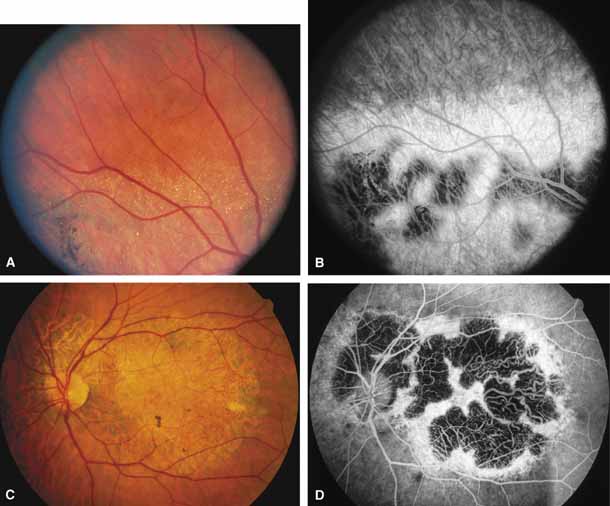

Serpiginous choroidopathy, also called serpiginous choroiditis, is a recurrent, progressive, destructive chronic degeneration of the choroid and retinal pigment epithelium that begins around the optic nerve and extends through the posterior pole.44 Unfortunately, some cases of this disorder have been reported under the name geographic helicoid peripapillary choroidopathy, and this has led to confusion with the clearly dominantly inherited genetic disorder first described in Iceland by Sveinsson26 in 1939 as choroiditis areata and subsequently renamed helicoidal peripapillary chorioretinal degeneration.27,28 The etiology of serpiginous choroidopathy is unknown, but the disease is not thought to be genetic. The disease starts as a gray, cream, or greenish discoloration and edema of the retinal pigment epithelium, followed by extension of the lesion, usually away from the disc, in a stepwise fashion (Figs. 8A and 8B). Vitritis is present in one-third of cases. Periods of quiescence or activity can be separated by months to years. Subretinal fibrous scarring, atrophy of the choroid, and hyperpigmentation in adjacent tissues can be prominent features (Figs. 8C and 8D). The prognosis for retention of central vision is poor because the disease process will often involve the macula. Systemic immunosuppression may be effective in prolonging remission and improving the visual outcome.45